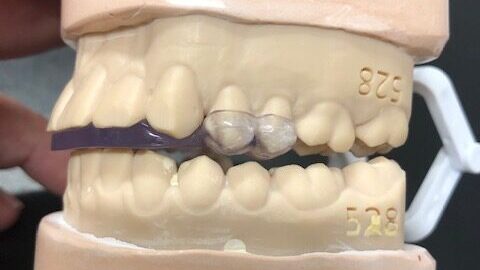

Urbanek TMJ Device Announces Launch Of Commercial Operations

The Urbanek TMJ Device and Protocol announced the official launch of its commercial operations in North America, offering dentists a new way to treat the 10+ million TMD/TMJ sufferers in the United States. “After more than 4,000 cases treated with a 95% success rate, we’re excited to finally offer this solution nationwide to treat the … Read more